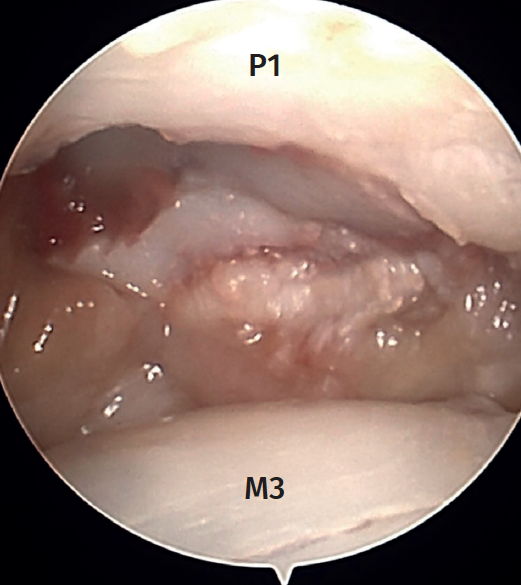

Arthroscopy of the MCP joint allows extensive visualization of the metacarpal head and the base of the proximal phalanx (Figure 1).

In the case of the thumb and sometimes on the radial side of the index finger, we can visualize the sesamoid bones. The radial and ulnar collateral ligaments as well as the accessory ligaments in a more volar position are clearly visible in all the fingers(1). The trajectory of the ligaments can be followed to their origin on both sides of the metacarpal head(2). The insertion of the ligaments at the base of the proximal phalanx is often injured after trauma, and we therefore must be able to identify this.

Thus, the anatomical landmarks to be recognized are, on the one hand, the extensor apparatus, which will serve as a reference for the arthroscopic portals; and, on the other hand, the joint structures themselves, which will be the ones we can visualize during the arthroscopic examination: metacarpal head, base of the proximal phalanx, volar capsule, main and accessory collateral ligaments, and dorsal capsule.